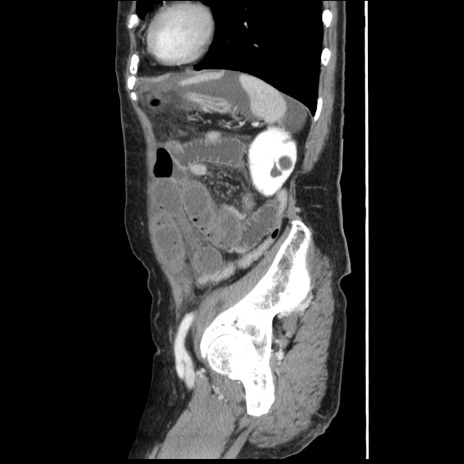

症例1(矢状断像)

【症例】80歳代女性

【主訴】腹痛

【現病歴】8時間前から腹痛あり来院。

【既往歴】糖尿病、脂質異常症、子宮体癌にて子宮全摘術

【身体所見】意識清明・会話良好だが腹痛で苦悶様、全腹部にわたって反跳痛と圧痛あり

【データ】WBC 13600、CRP 0.14、LDH 224、CK 90